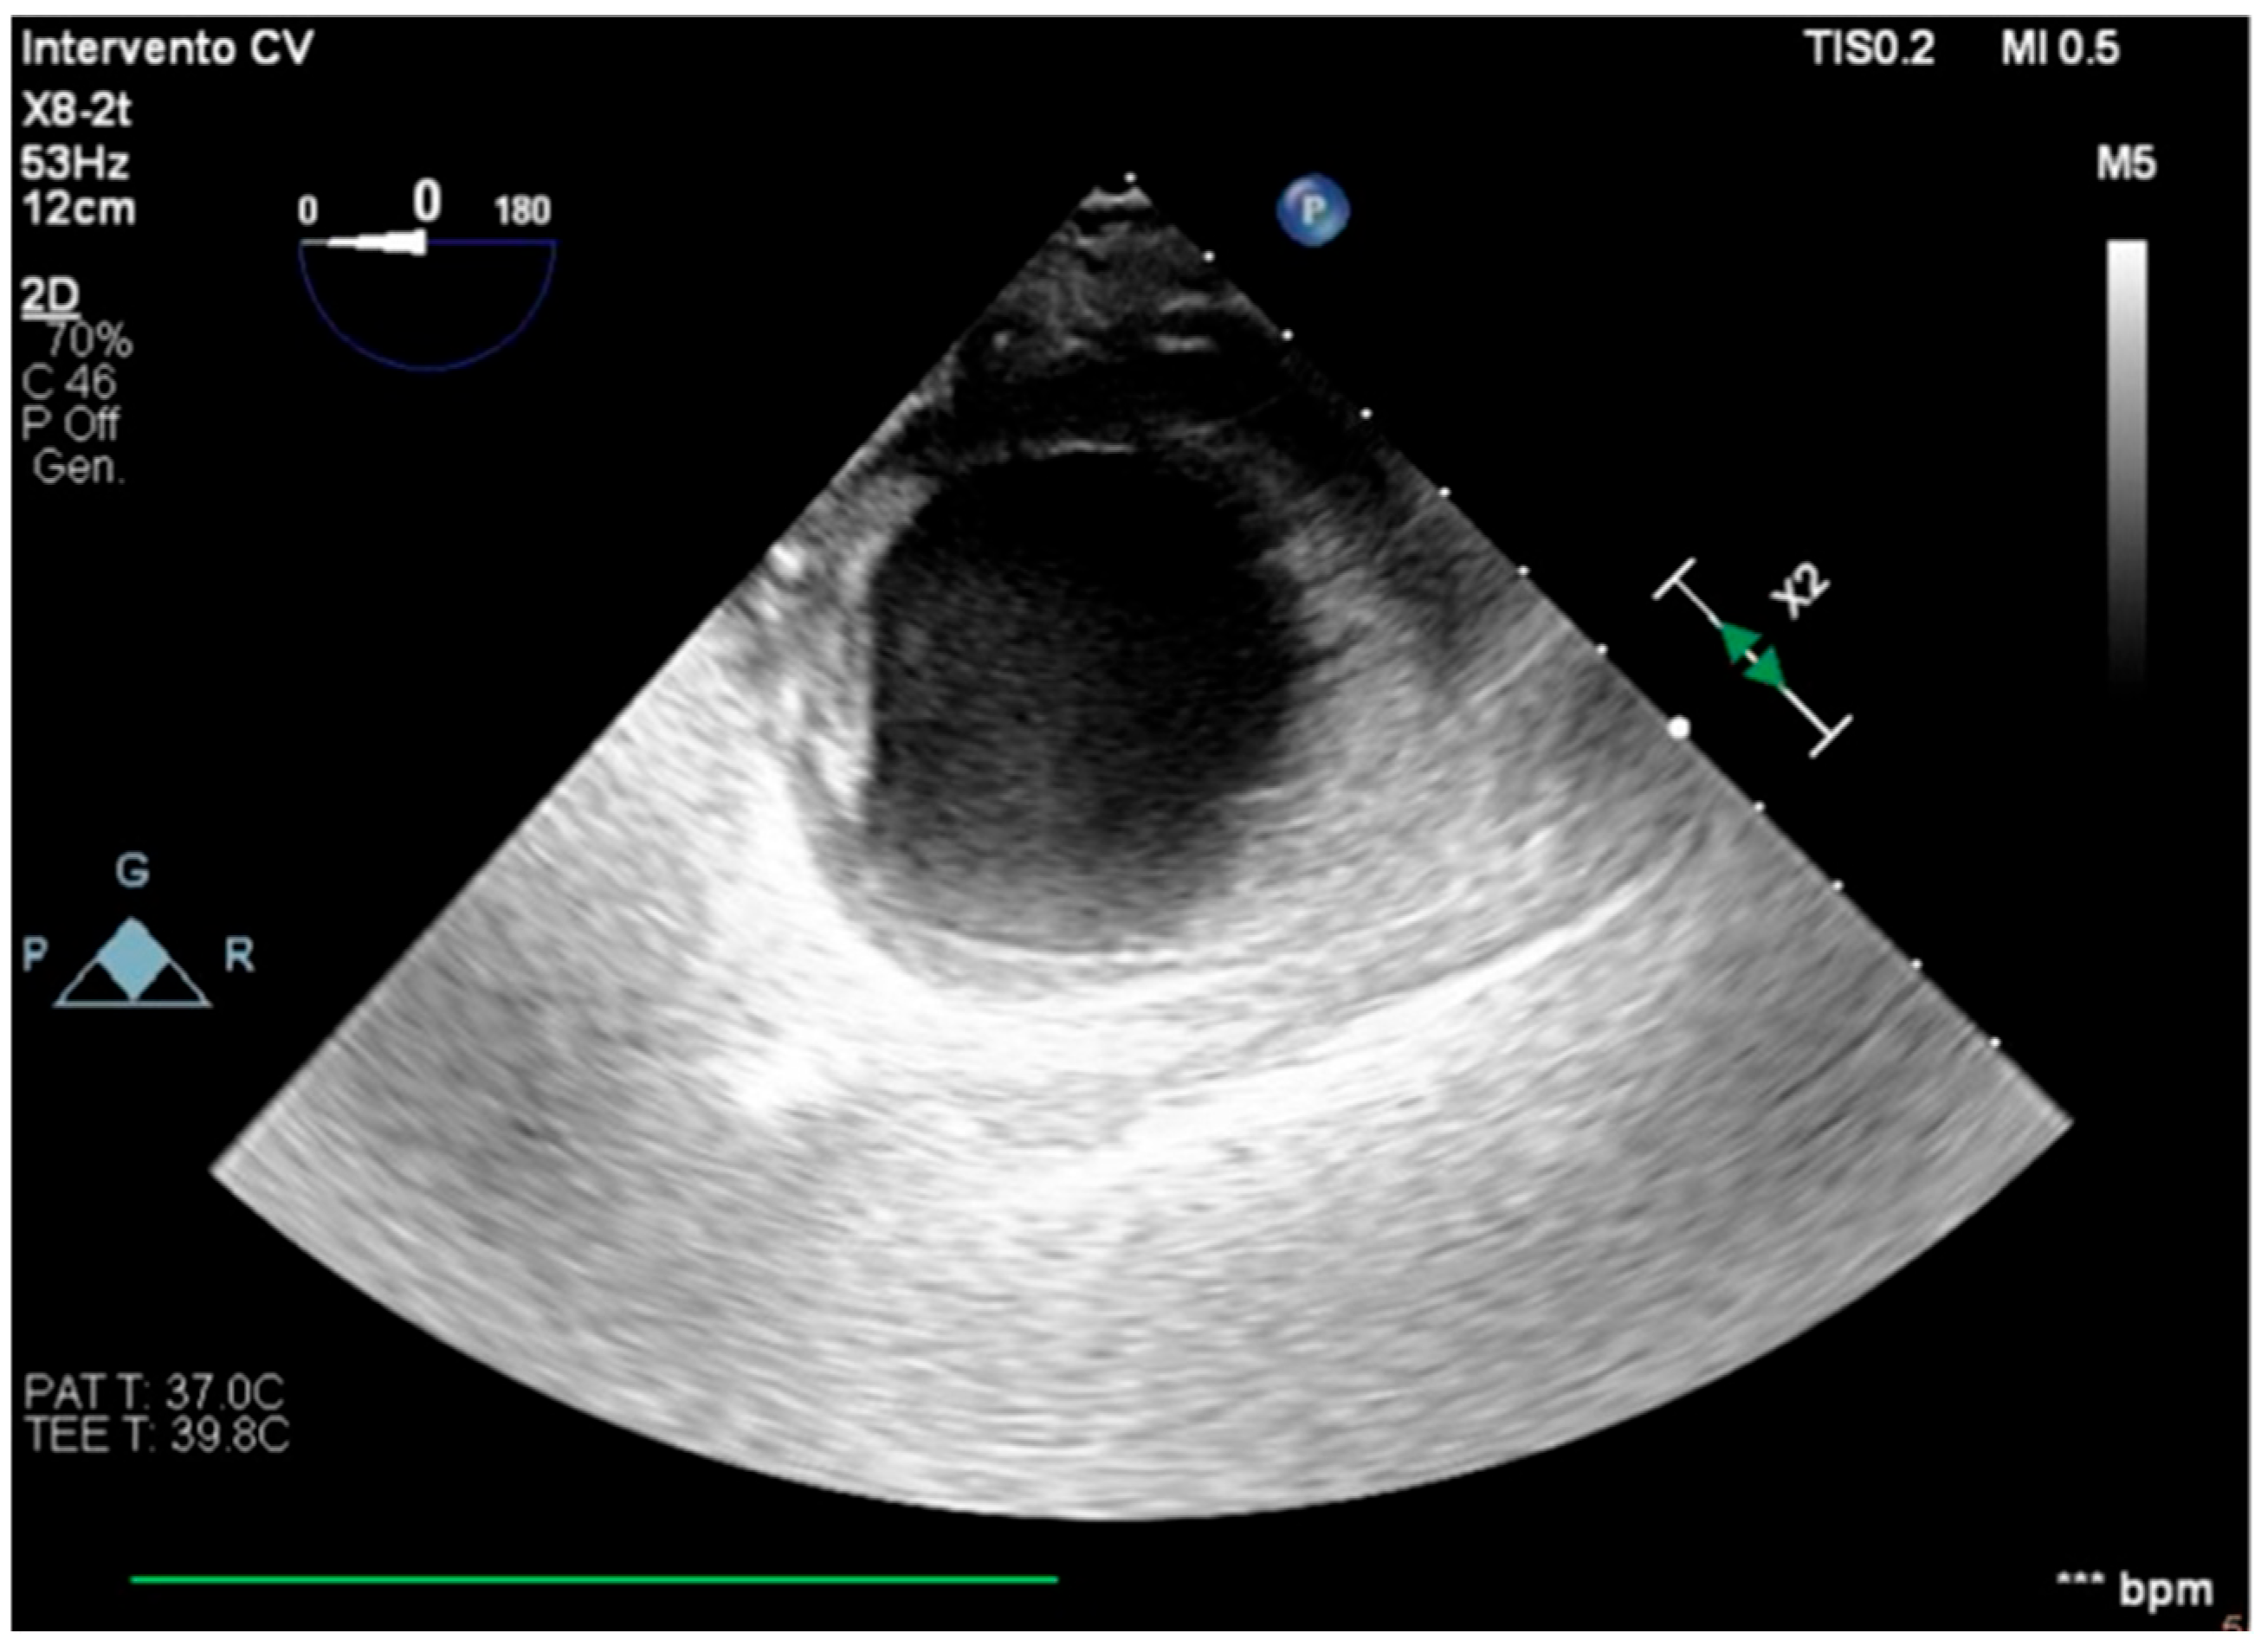

The transesophageal echocardiography showed LVOT-VTI 10 cm; apical, septal, and anterior wall akinesia; preserved function of the medium-basal segments of the inferior and lateral walls (Figure 3, Figure 4 and Figure 5); and RV-FAC 39% with an unloaded right ventricle (Figure 6).

Figure 3. TG mid-papillary level, the day after surgery (T0).